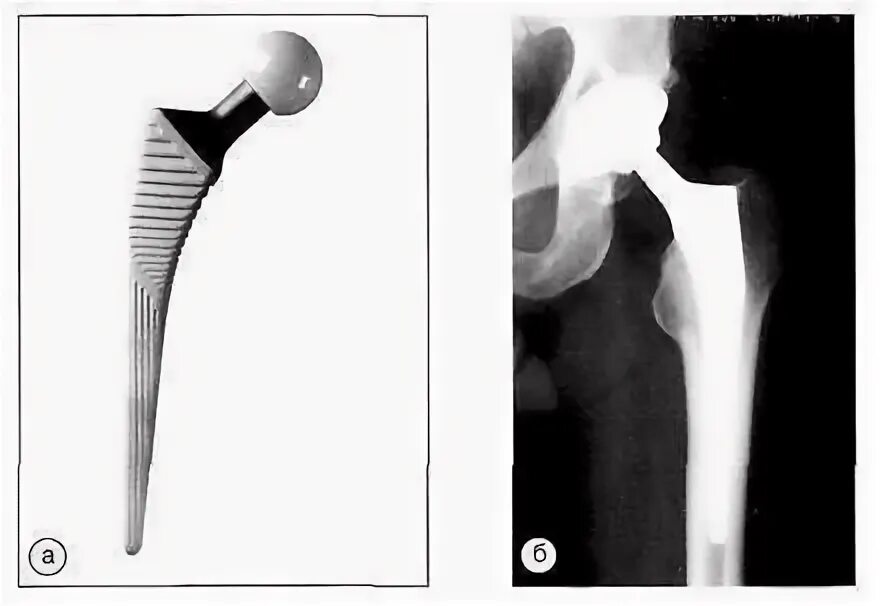

Можно ли эндопротезом делать мрт